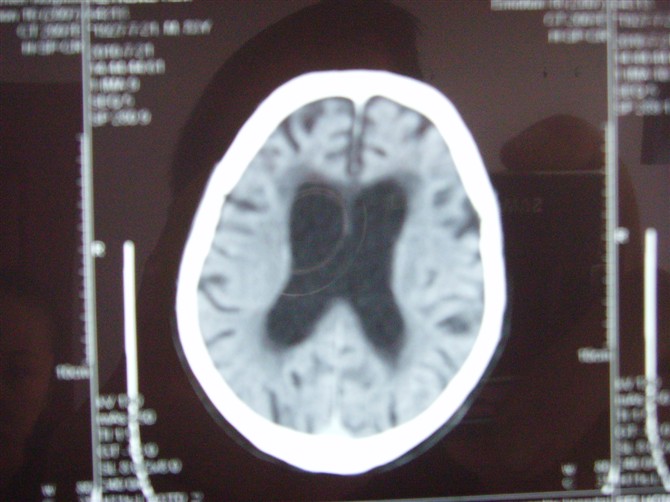

标题: CT27993:男 83岁 头晕伴双下肢无力一天 [打印本页]

标题: CT27993:男 83岁 头晕伴双下肢无力一天

脑白质疏松症,脑萎缩,复查

脑萎缩。伴小脑齿状核、苍白球钙化.脑白质脱髓鞘病变

脑白质疏松症,脑萎缩!

脑萎缩,脑白质疏松症。

1)双侧小脑半球脑软化灶。2)全脑萎缩。3)脑白质病。